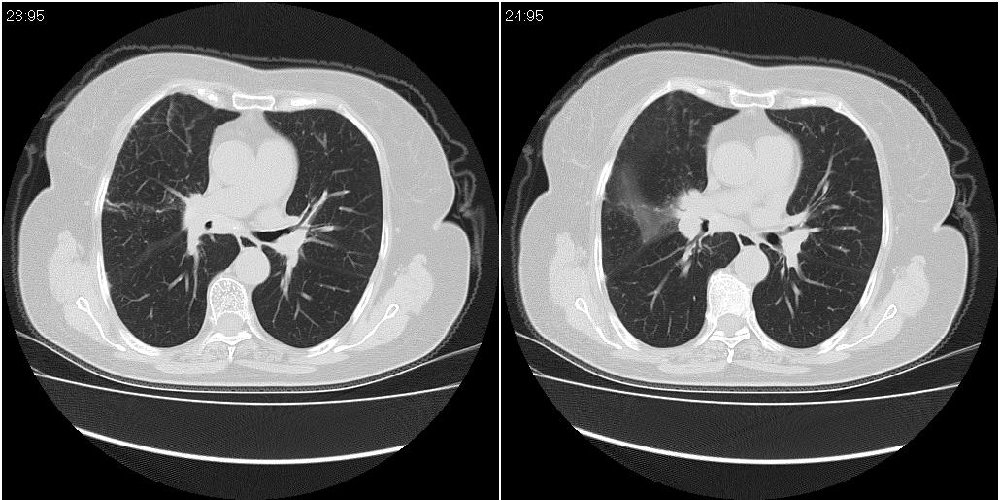

女性,72岁。去年9月份发现肺部病变,诊为肺结核并进行正规治疗至今,但复查后发现ct表现几乎没有变化。

右中间段支气管局限性狭窄,右中叶支气管亦稍显狭窄,但并未见明显占位表现,半年多了,无变化也许是好事,可能为炎性狭窄,建议继续随访。

双肺继发型tb并右中叶内膜tb,轻度支扩,左下胸膜肥厚粘连。

右中叶炎性改变,支气管狭窄但较光滑,占位可能性不大。

右中间段支气管局限性狭窄,右中叶支气管亦稍显狭窄.

双肺继发性肺结核并右肺中叶节段性肺不张,左下胸膜肥厚粘连。

右肺中叶节段性肺不张,考虑结核或慢性炎症,建议做纤支镜检查。

双肺继发性肺结核并右肺中叶节段性肺不张